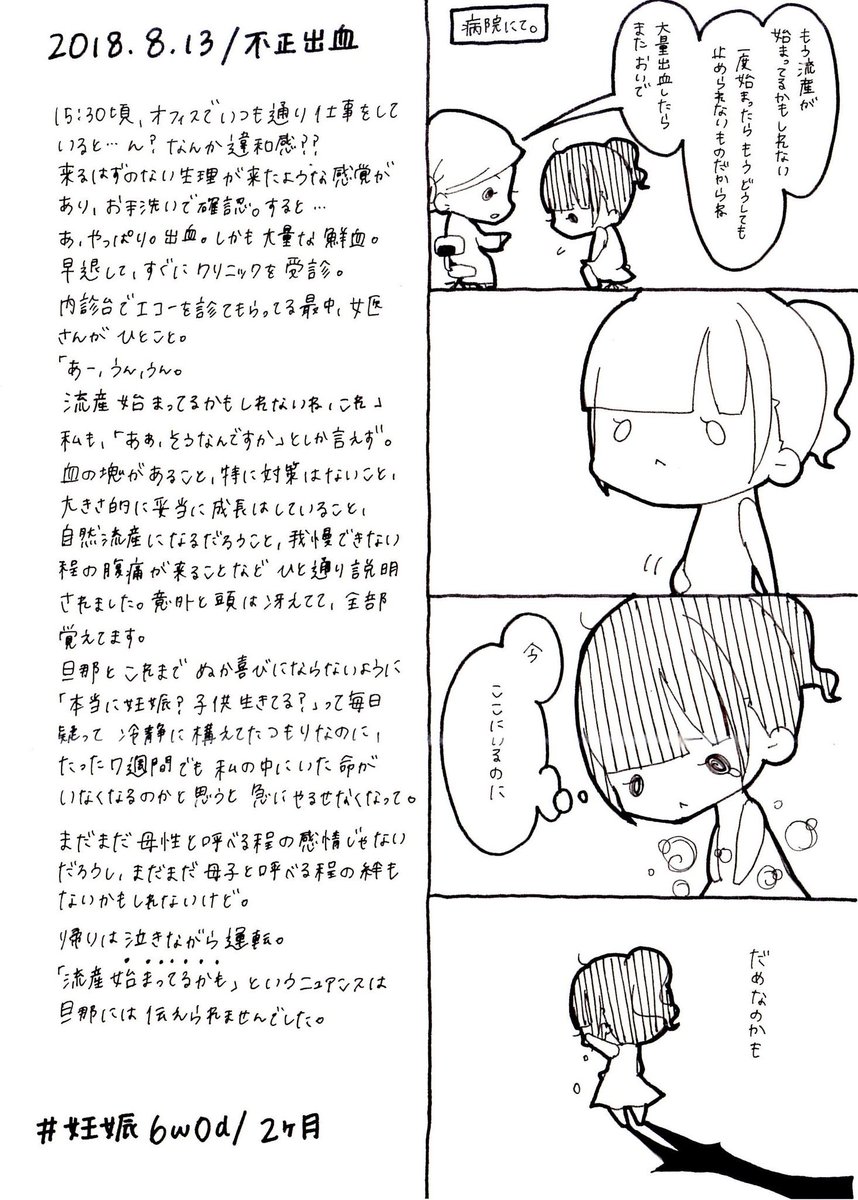

2018.8.13 不正出血からの流産待ち宣告。 たった数週間でも私の中にいた生命が消えるかも…と思うと、悲しくて悔しくて。 #育児漫画 #育児日記 #妊娠 #妊娠初期 #不正出血 pic.twitter.com/ip8xEUOnpv